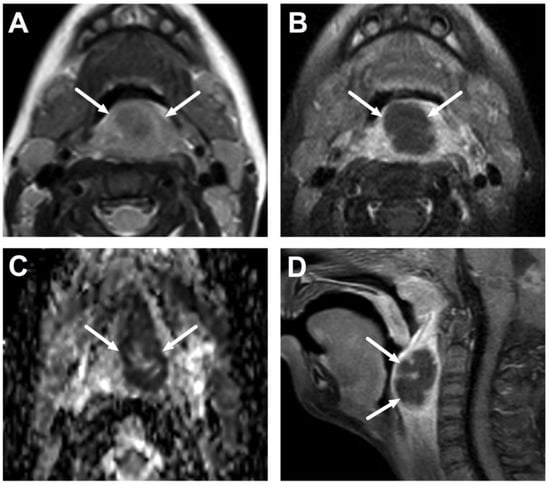

4.3. Oral Cavity

4.4. Sialadenitis

| Abscess | T1 SE T2 Dixon (water) DWI post-contrast T1 Dixon (water) | Non-enhancing collection with low ADC values enclosed in abnormally enhancing soft tissue edema. | Detection of an abscess usually requires operative consideration and exact abscess location, and extensions are useful in operative planning. | Abscesses may have an intermediate T2 signal content; blood products and/or postoperative status may complicate abscess assessment; necrotic lymph nodes may be misinterpreted as suppurative lymphadenitis. |